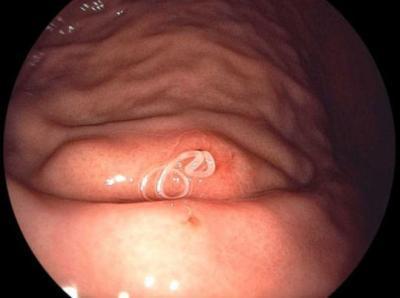

アニサキスはヒトの体内では成虫にはなれないということなので、私たちが生魚を食して影響を受けるのは成虫前の段階ということになります。おおよそ2センチ~3センチの大きさで渦巻き状になっていることが多く、半透明粘膜の袋(シスト)に入っていることもあるそうです。

◆アニサキス症状の予防方法②:色と状態を目視確認!少し赤色?渦?どこにいるの?サバ画像付き

アニサキスは表面に少しでも出ていれば、目視で確認ができる寄生虫と言われています。糸状の形態をしていて渦を巻いていることが多いです。体長は約2センチから3センチ、色は半透明白色であり、状況によっては下記のように赤っぽく見えることもありますが基本的には本来、白色の糸のように見えるようです。